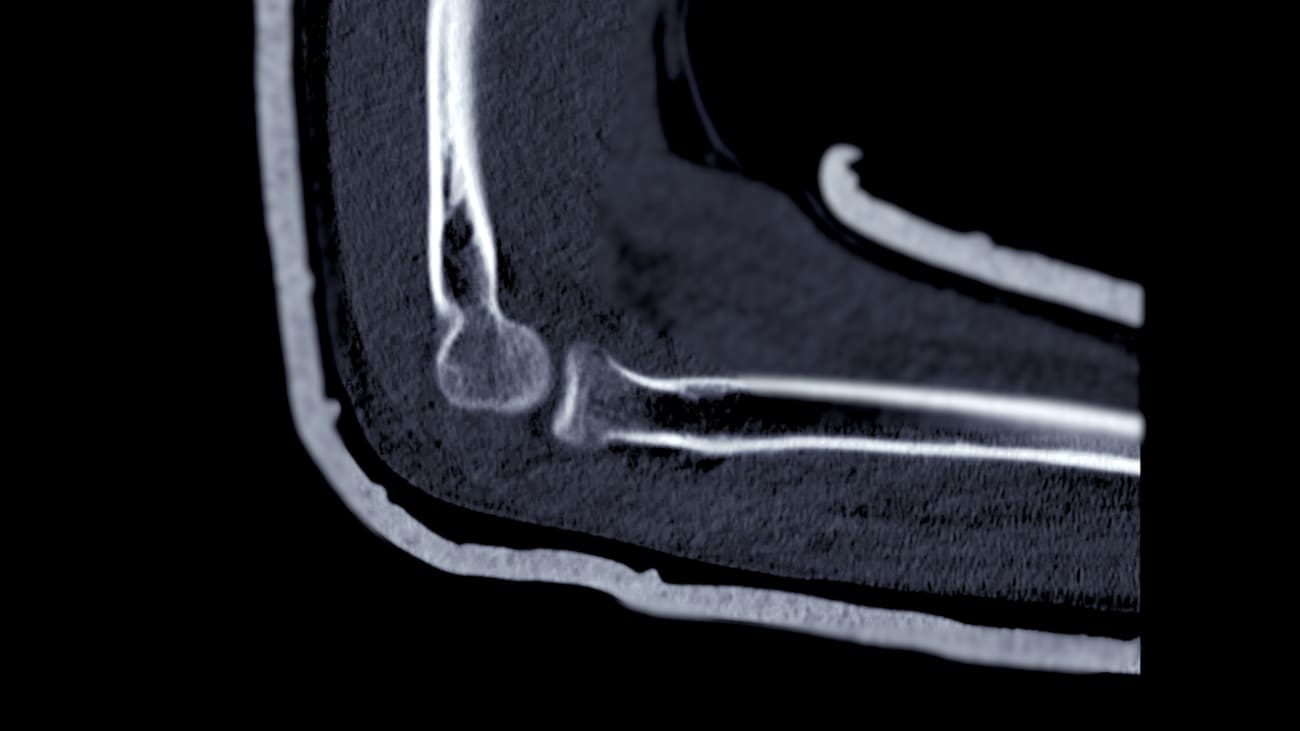

Imaging, including MRI, combined with careful physical examination and assessment of athlete goals, informs this decision-making process.